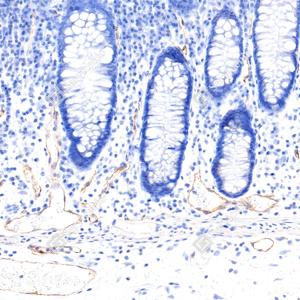

| IHC检测TMEM16A/DOG1蛋白(货号 GB15920). 样品: 人结肠, 4%多聚甲醛 (货号G1101) 固定12-24小时. 抗原修复: 抗原修复仪(货号 ARI-4),Tris-EDTA抗原修复液(pH 9.0) (货号G1203), 水浴100℃, 25分钟. —抗: 1: 2000稀释, 4℃ 孵育过夜. 二抗: S-vision免疫组化多聚二抗(山羊抗兔),即用型 (货号G1302), 室温孵育20分钟. |